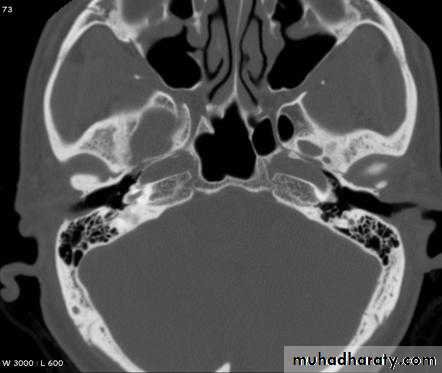

Type As “ stiff ” tympanogramCT scan: to assess extent of otosclerosis.